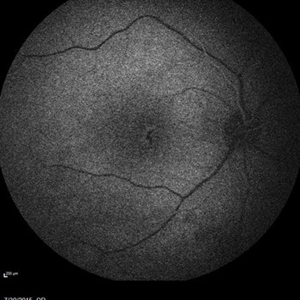

Retinal Dystrophy of 24-Year-Old Male Mid FA OD

Fluorescein angiography of a 24-year-old male. Juvenile retinoschisis on OCT. FA shows outer retinal staining. Could be associated with Goldman Farve Syndrome.

Photographer: Zach Dupureur, OCT-C

Condition/keywords: Goldmann-Favre Syndrome, juvenile retinoschisis, retinal dystrophy